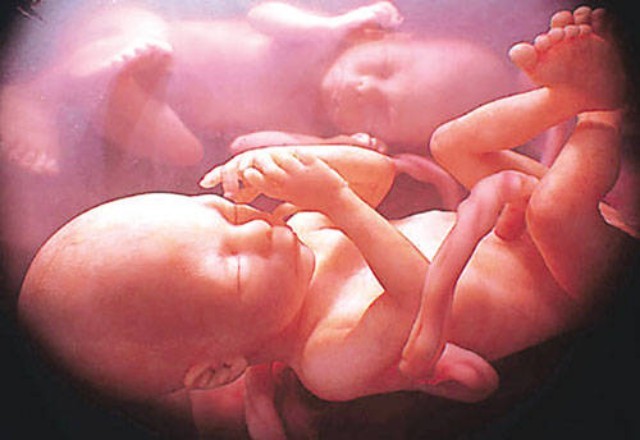

(ворушіння при вагітності близнюками на терміні 6.5 місяців)

Як відбувається вагітність близнюками? Справа в тому, що іноді в момент зачаття відбувається запліднення двох яйцеклітин, і обидві вони виживають, прикріплюються до стінки матки, і починають свій розвиток. Ще одна причина отримання двійні – поділ однієї заплідненої яйцеклітини на два ембріона.